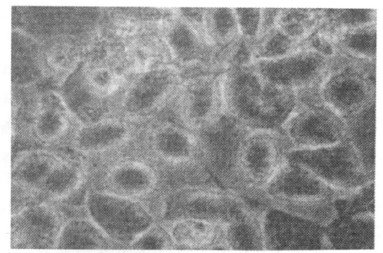

2.2 胎盘滋养层细胞系Bewo形态(图 1, 2)

图 1 人胎盘滋养层细胞来源的Bewo细胞(培养第2 d, 200×) |

倒置显微镜下观察, Bewo细胞接种2 h后开始贴壁, 24 h绝大多数细胞明显贴壁。贴壁的Bewo细胞呈立方多角形或圆形、卵圆形, 细胞核大、较圆; 传代1 d后细胞进入对数生长期, 细胞分裂相增多。